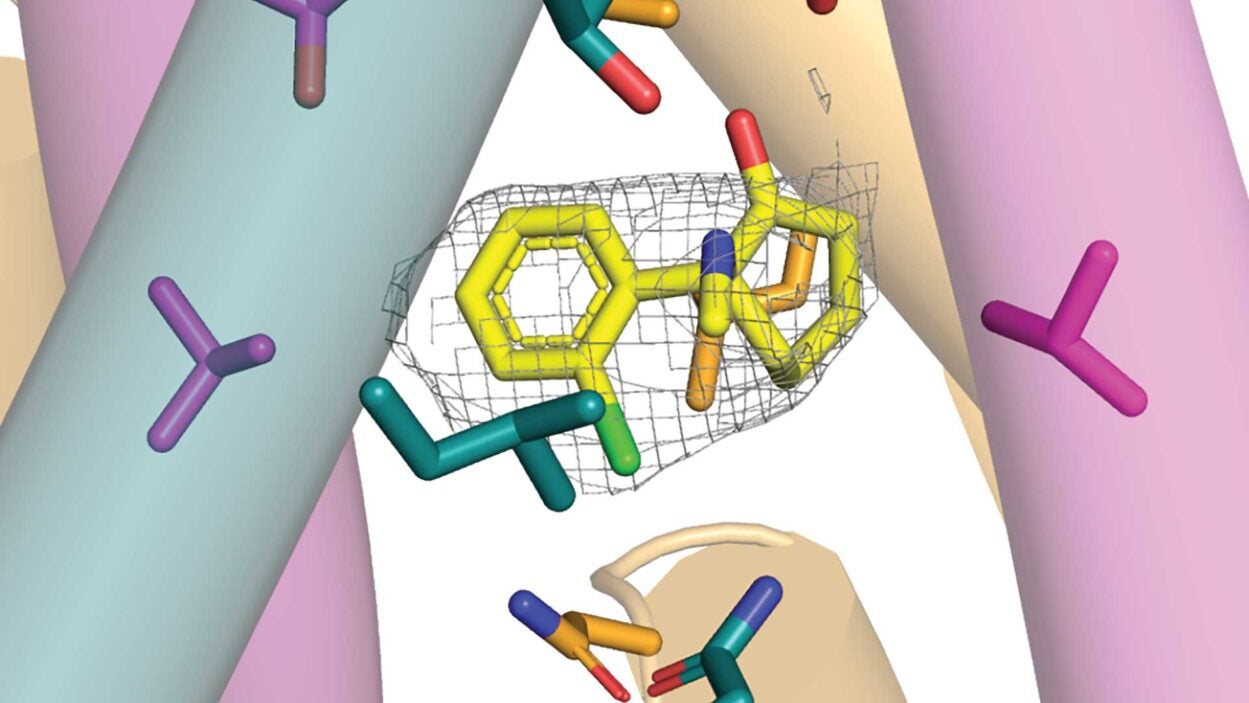

CSHL Professor Hiro Furukawa proves the existence of a mysterious brain receptor known as GluN1-2B-2D and shows how it may interact with ketamine. Read the story »

CSHL Professor Hiro Furukawa sheds new light on anti-NMDAR encephalitis, a rare autoimmune disorder that may be misdiagnosed as schizophrenia. Read the story »

CSHL Professor Hiro Furukawa has figured out how the NMDAR performs a key step in the brain’s cognitive dance. Read the story »